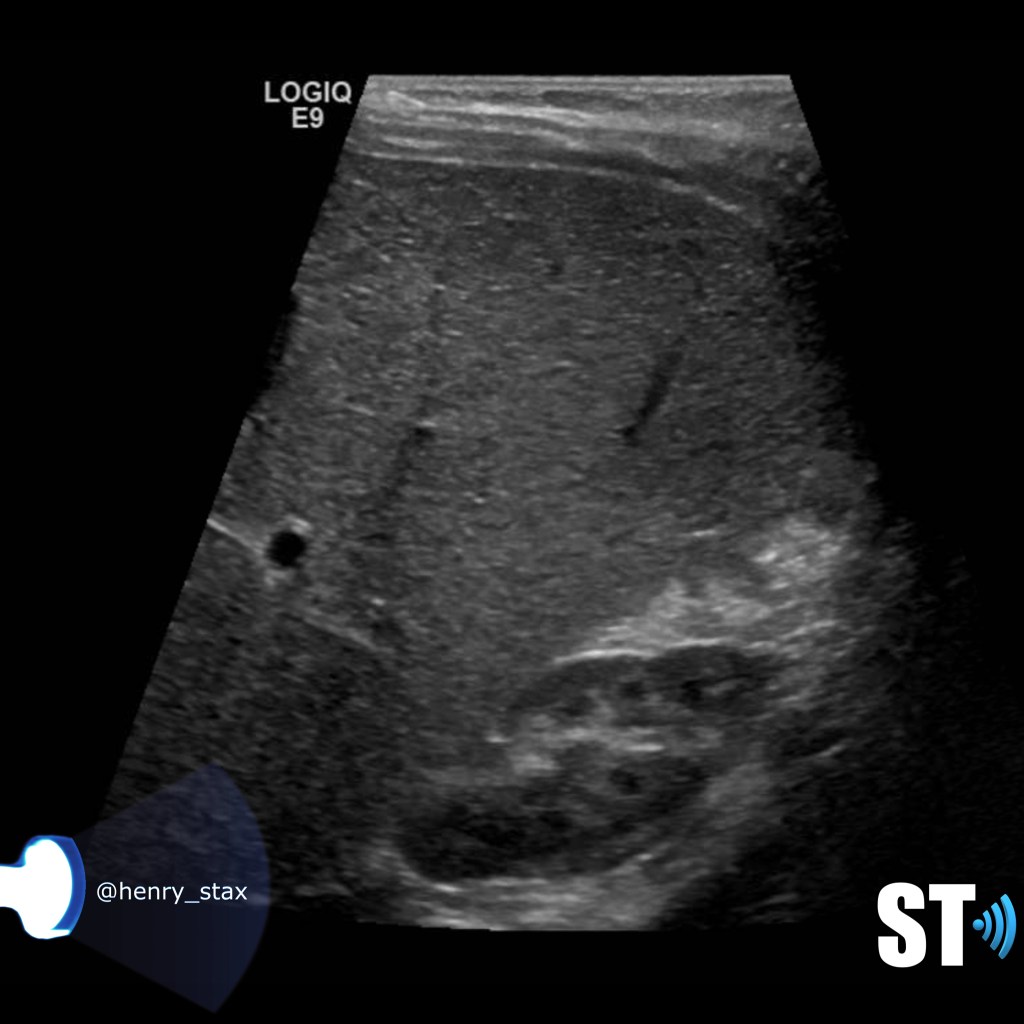

ADPKD

In Autosomal Dominant Polycystic Kidney Disease (ADPKD) the kidneys are normal at birth with cysts developing overtime. By age 30 years, approximately 68% of patients will have visible cysts by ultrasound. Eventually, virtually all patients develop cysts. The disease is transmitted in an autosomal dominant pattern, meaning you only one abnormal gene from one parent.

One abnormal gene from one parent

- Adult

- 4-10% of all cases of ESRF

- Kidneys appear normal early on

- Liver, pancreas and spleen cysts